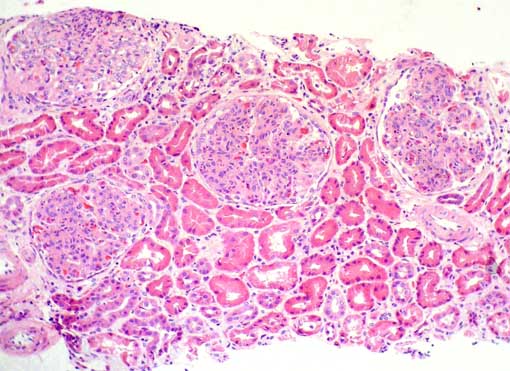

Figure 1.

H&E, X100.